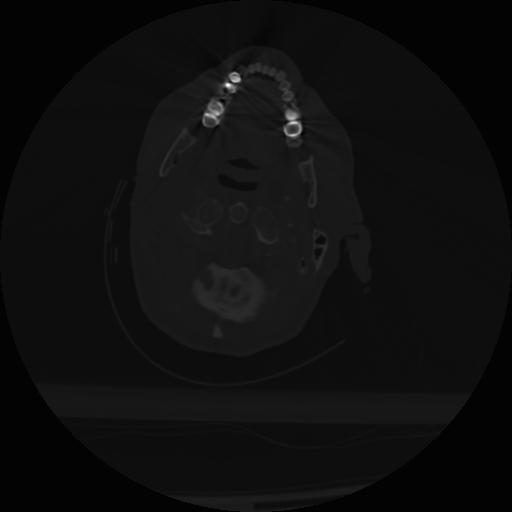

22 ANGIO,CE,Vol,0.5,ANGIO,,